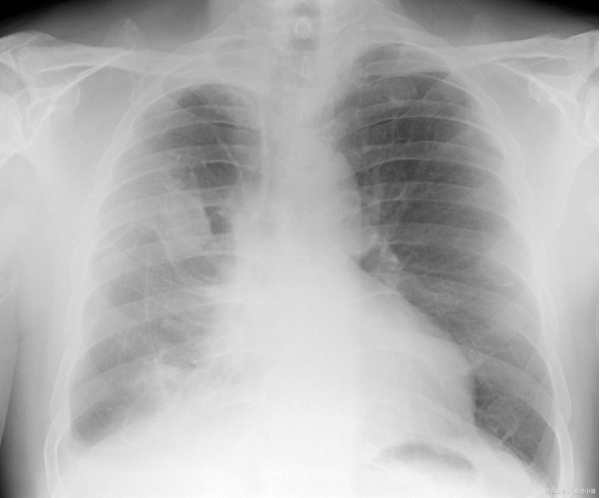

影像学检查结果让所有医生倒吸一口凉气:CT显示小雅的腹腔内布满大小不一的肿瘤,最大的直径20厘米,从胃部一直延伸到盆腔,几乎占据了整个腹腔空间。"肿瘤已经压迫到肠道,导致便血;压迫神经,引发剧烈腹痛。"该院肿瘤科主任张华教授指着影像片解释,"更危险的是,肿瘤靠近大血管,随时可能破裂出血,危及生命。"